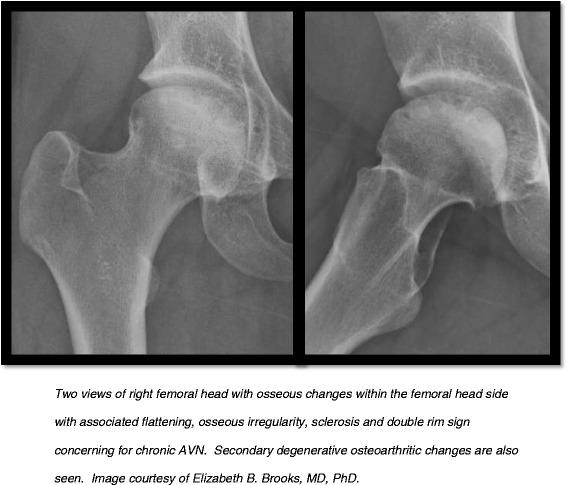

https://cdn.ncbi.nlm.nih.gov/pmc/blobs/458b/4415214/5ea507790d0e/12969_2015_8_Fig1_HTML.jpg